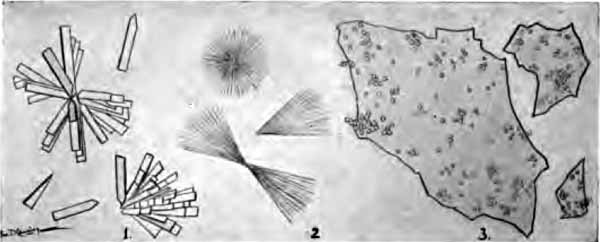

The more important structures to be seen in unstained sputum are: elastic fibers, Curschmann's spirals, [p. 27] Charcot-Leyden crystals, fibrinous casts, the ray fungus of actinomycosis, and molds. Pigmented cells, especially the so-called "heart-failure cells" (p. 43), are also best studied without staining (Plate II, Fig. 1).

Elastic fibers from the sputum

FIG. 4.—Elastic fibers from the sputum: a, Highly magnified; b, alveolar arrangement, less highly magnified (after Bizzozero).

Curschmann's spirals

FIG. 5.—Curschmann's spirals: I., Natural size; II. and III., enlarged: a, central fiber (after Curschmann).

2. Curschmann's Spirals.—These peculiar structures are found most frequently in bronchial asthma, of which they are fairly characteristic. They may occasionally be met with in chronic bronchitis and other conditions. Their nature has not been definitely determined.

Macroscopically, they are whitish or yellow, twisted threads, frequently coiled into little balls (Fig. 5, I.). Their length is rarely over half an inch, though it sometimes exceeds two inches. Under a two-thirds objective they appear as mucous threads having a clear central fiber, about which are wound many fine fibrils (Fig. 5, II. and III.). Leukocytes are usually present within them, and sometimes Charcot-Leyden crystals. The central fiber is not always present.

Charcot-Leyden crystals

FIG. 6.—Charcot-Leyden crystals (after Riegel).

[p. 30] 3. Charcot-Leyden Crystals.—Of the crystals which may be found in the sputum, the most interesting are the Charcot-Leyden crystals. They are rarely found except in cases of bronchial asthma, and were at one time thought to be the cause of the disease. They frequently adhere to Curschmann spirals. Their exact nature is unknown.

They are colorless, pointed, often needle-like, octahedral crystals (Fig. 6). Their size varies greatly, the average length being about three or four times the diameter of a red blood-corpuscle.

Sputum from a case of actinomycosis

FIG. 8.—Sputum from a case of actinomycosis; stained (Jakob).

5. Actinomyces Bovis (Ray-fungus).—In the sputum of pulmonary actinomycosis and in the pus from actinomycotic lesions elsewhere small, yellowish, "sulphur" granules can be detected with the unaided eye. The fungus can be seen by crushing one of these granules between slide and cover, and examining with a low power. It consists of a network of threads having a more or less radial arrangement, those at the periphery presenting club-shaped extremities (Fig. 8). This organism, also called Streptothrix actinomyces, apparently stands midway between the bacteria and the molds. It stains by Gram's method.